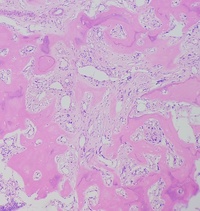

Primary myelofibrosis (PMF) with osteosclerotic progression 1

Primary myelofibrosis (PMF) with osteosclerotic progression. Patient presented with pancytopenia and massive splenomegaly